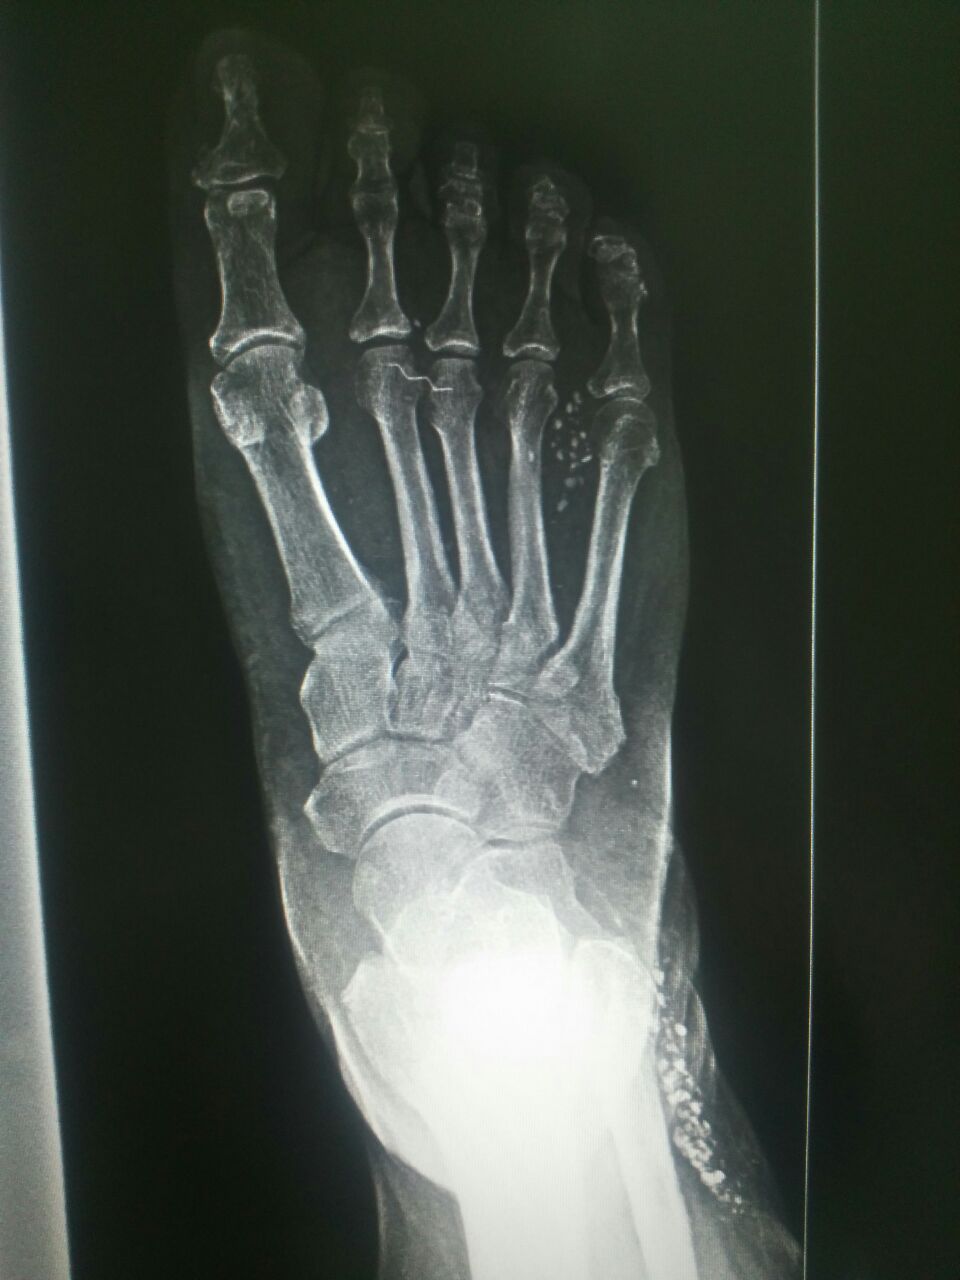

Здравствуйте. Ж 1956 г.р.

Коллеги как оценить кальцификаты

Не похож на кальцификации

Не оскольки?

Дробинки?

Что за проволока...

Это по моему травма... Производственная новерно...

А ещё в области малоберцовой что-то